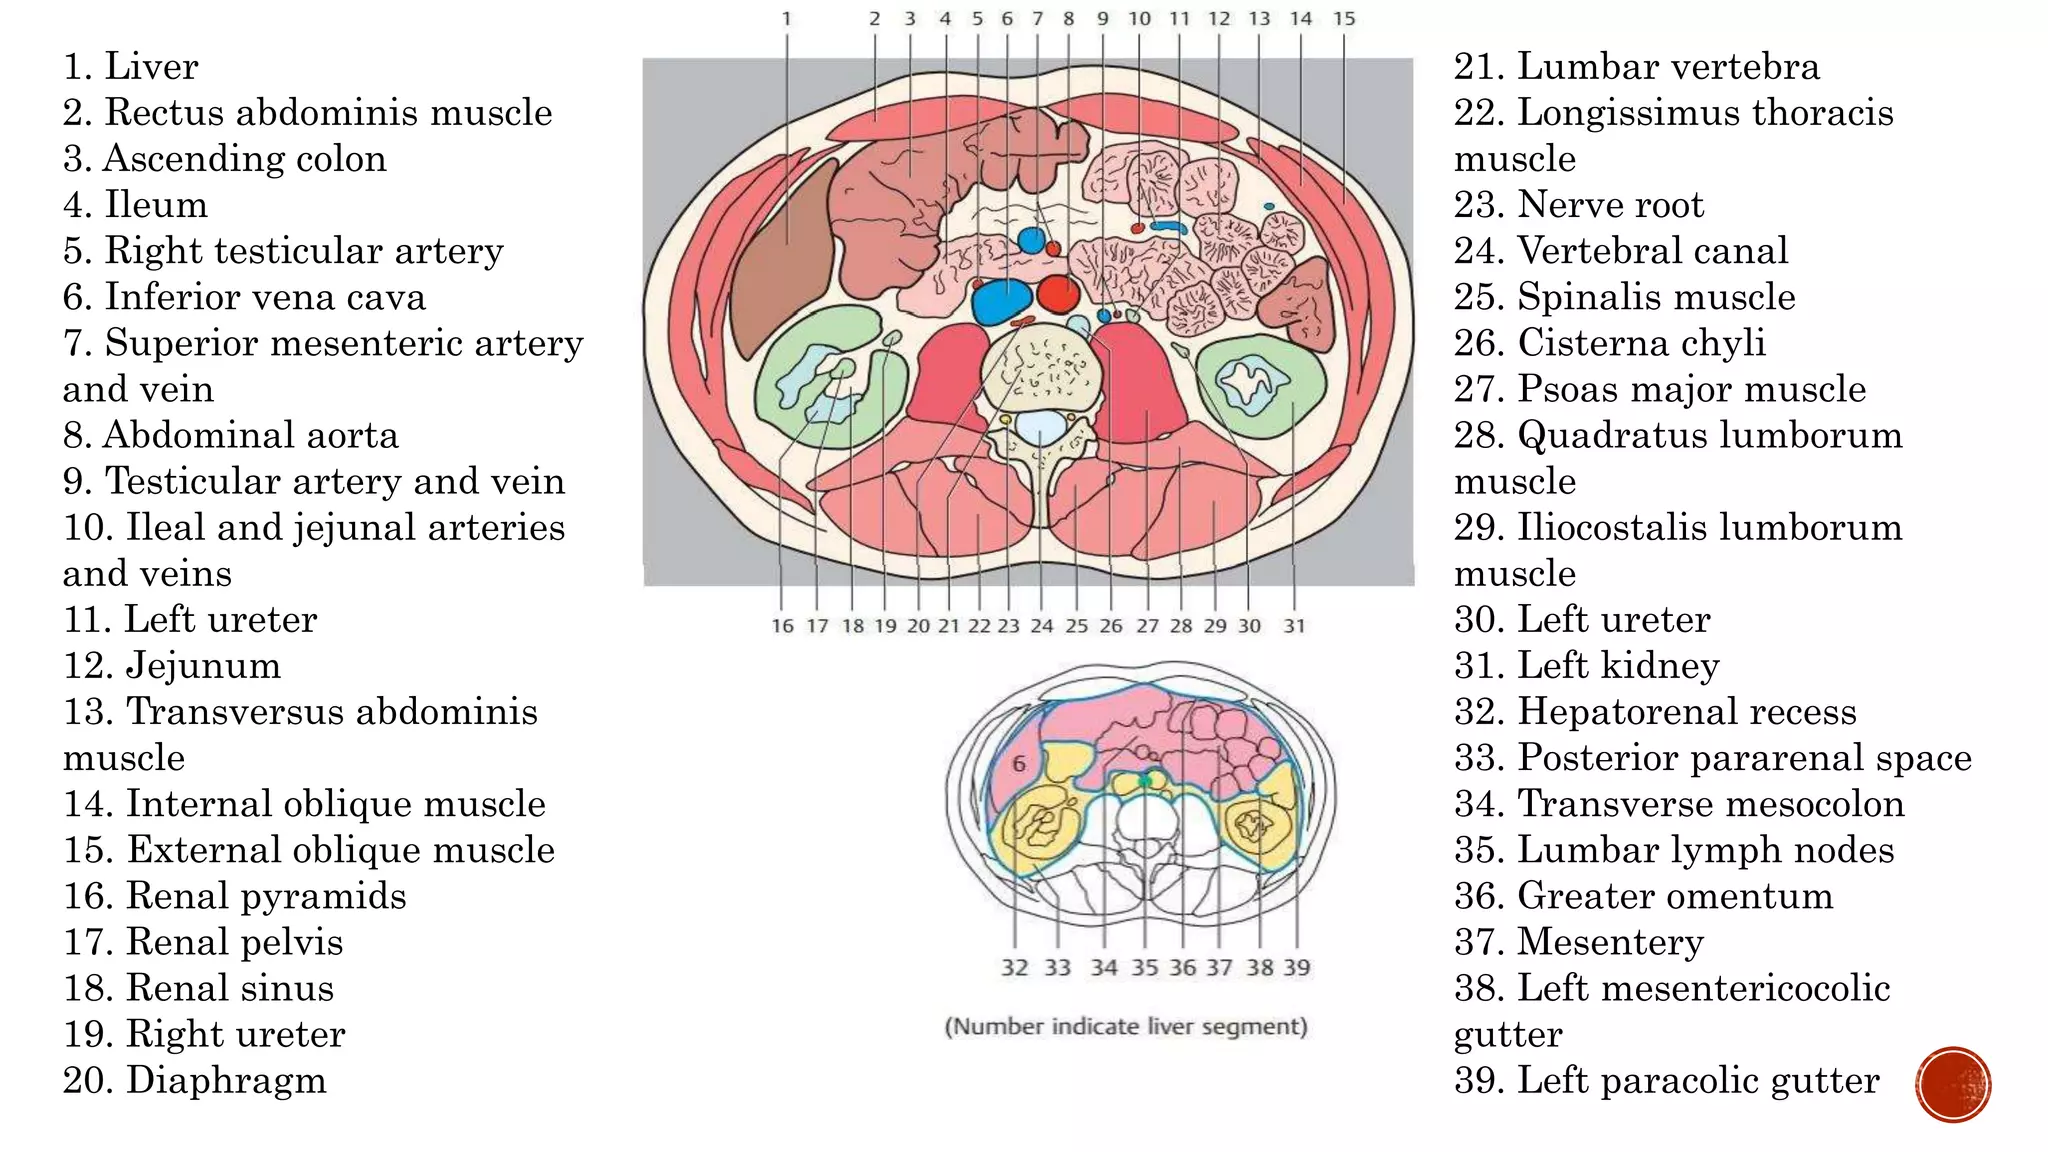

The document describes the anatomy of the abdomen and pelvis region of the human body. It lists over 40 structures and their locations, including major organs like the liver, kidneys, intestines, blood vessels and muscles of the abdominal wall and pelvis. The structures are grouped into sections focusing on different anatomical areas like the abdomen, retroperitoneum, pelvis and gluteal region.